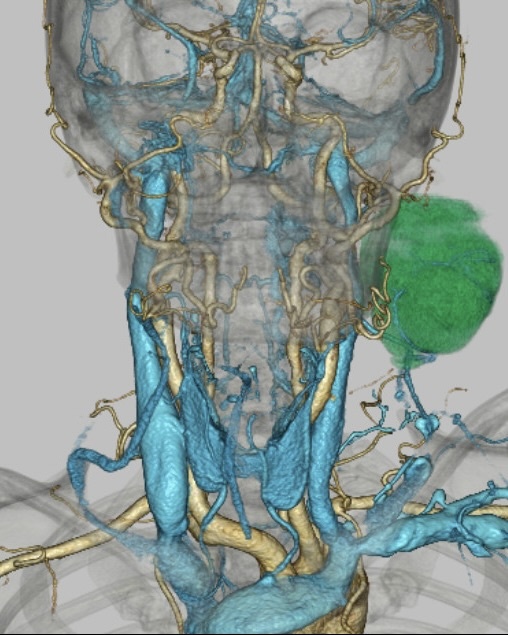

手術支援

手術支援3D画像(頸部)